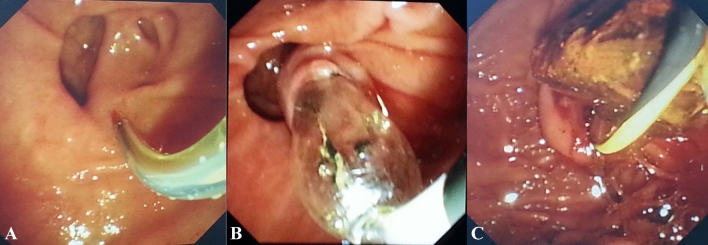

Selective cannulation of the CBD was performed by a sphincterotome with a guidewire. The double-guidewire technique or the transpancreatic precut was applied in some difficult cases, such as inflammation or special morphology of papilla, and periampullary diverticula. For cases with CBD stones embedded within the papilla, needle-knife papillotomy was performed. For type B diverticula, we first exposed the papilla by eversion using biopsy forceps, or fixation by metal clip, or submucosal injection of saline, and the double-guidewire technique was often applied.

After cannulation of the CBD and cholangiography, endoscopic sphincterotomy (EST) alone or small EST combined with endoscopic papillary balloon dilation (EPBD) was performed. For cases with either abnormal coagulation (because of taking antiplatelet and anticoagulation medicine) or with type B diverticula, EPBD alone was performed.

Mechanical lithotripsy was applied when CBD stones were too large. However, if a patient was in poor condition or had large CBD stones with type B diverticula, endoscopic retrograde biliary drainage (ERBD) alone was performed. Three months later, when stones would have become smaller and softer, a subsequent ERCP was performed for removal of CBD stones.

The guidewire was always kept in bile duct during the whole procedure, and in most cases endoscopic nasobiliary drainage (ENBD) was placed after removal of CBD stones, especially in cases with mechanical lithotripsy. For cases with multiple pancreatic-duct cannulations, endoscopic retrograde pancreatic drainage (ERPD) was performed.